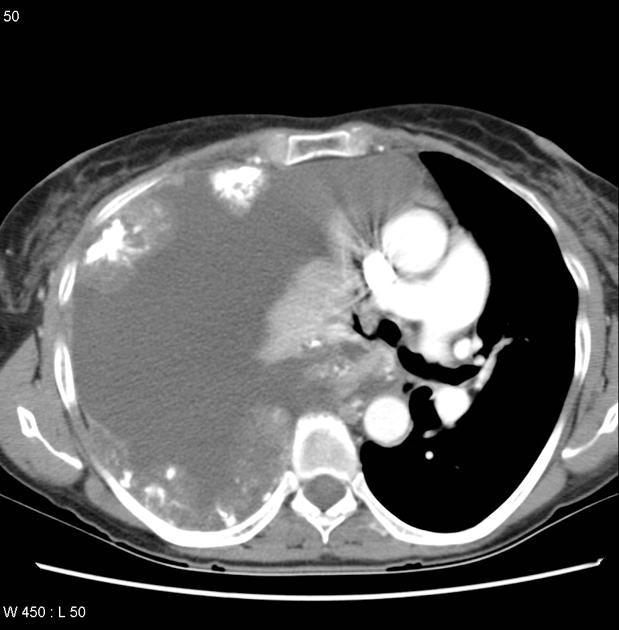

CT

Myxomas, as is the case with other cardiac tumors, appear as intracardiac masses, most often in the left atrium and attached to the interatrial septum. They are usually heterogeneously low attenuating (approximately two-thirds of cases 2,8). Due to repeated episodes of hemorrhage, dystrophic calcification is common 8.

If the mass is pedunculated, the motion within the heart can be demonstrated, including prolapse through the mitral valve.